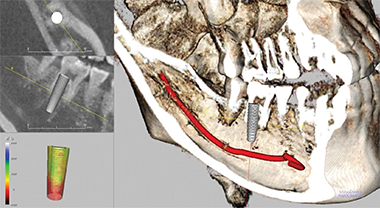

精密診断です。

3D CT撮影

体系的診断です。

総合的な治療計画です。

個人に合わせた設計です。

治療方法の選択です。

インプラント埋入です。

正確な位置にインプラントを埋入します。